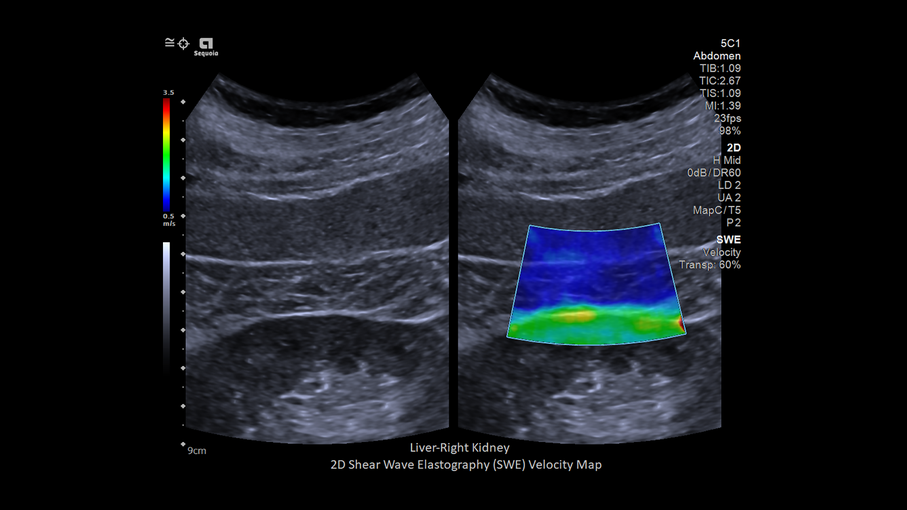

Кроме новой техники, можно заказать восстановленные медицинские системы: ультразвуковые сканеры, томографы, флюороскопы, ангиографы и хирургические установки С-дуга.